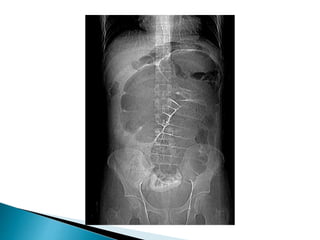

Inverted U-shaped appearance of distended

sigmoid loop

 Largest and most dilated loops of bowel are

seen with volvulus

 Loss of haustra

 Coffee-bean sign à midline crease

corresponding to mesenteric root in a greatly

distended sigmoid

 Sigmoid volvulus – bowel loop points to RUQ

large, dilated loop of large bowel with an inverted U-shape

with walls between two volvulated loops pointing from LLQ toward RUQ;

same patient with decompressed sigmoid volvulus following insertion of rectal tube